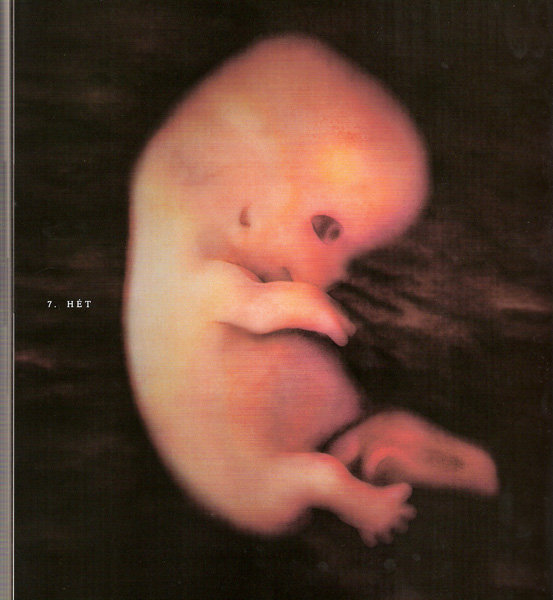

Annus nagyon jók a képek. kis ALien-nek néznek ki... szép az élet...

Annus, nem lehet, hogy a képen, amin 7. hét van. az a 7. terhességi héten készült, és nem a mensitől számítva, mert a táblázat szerint, amit a babanet küldnekem hetente az áll, hogy a 7 hét végén lesz kb 10 mm.